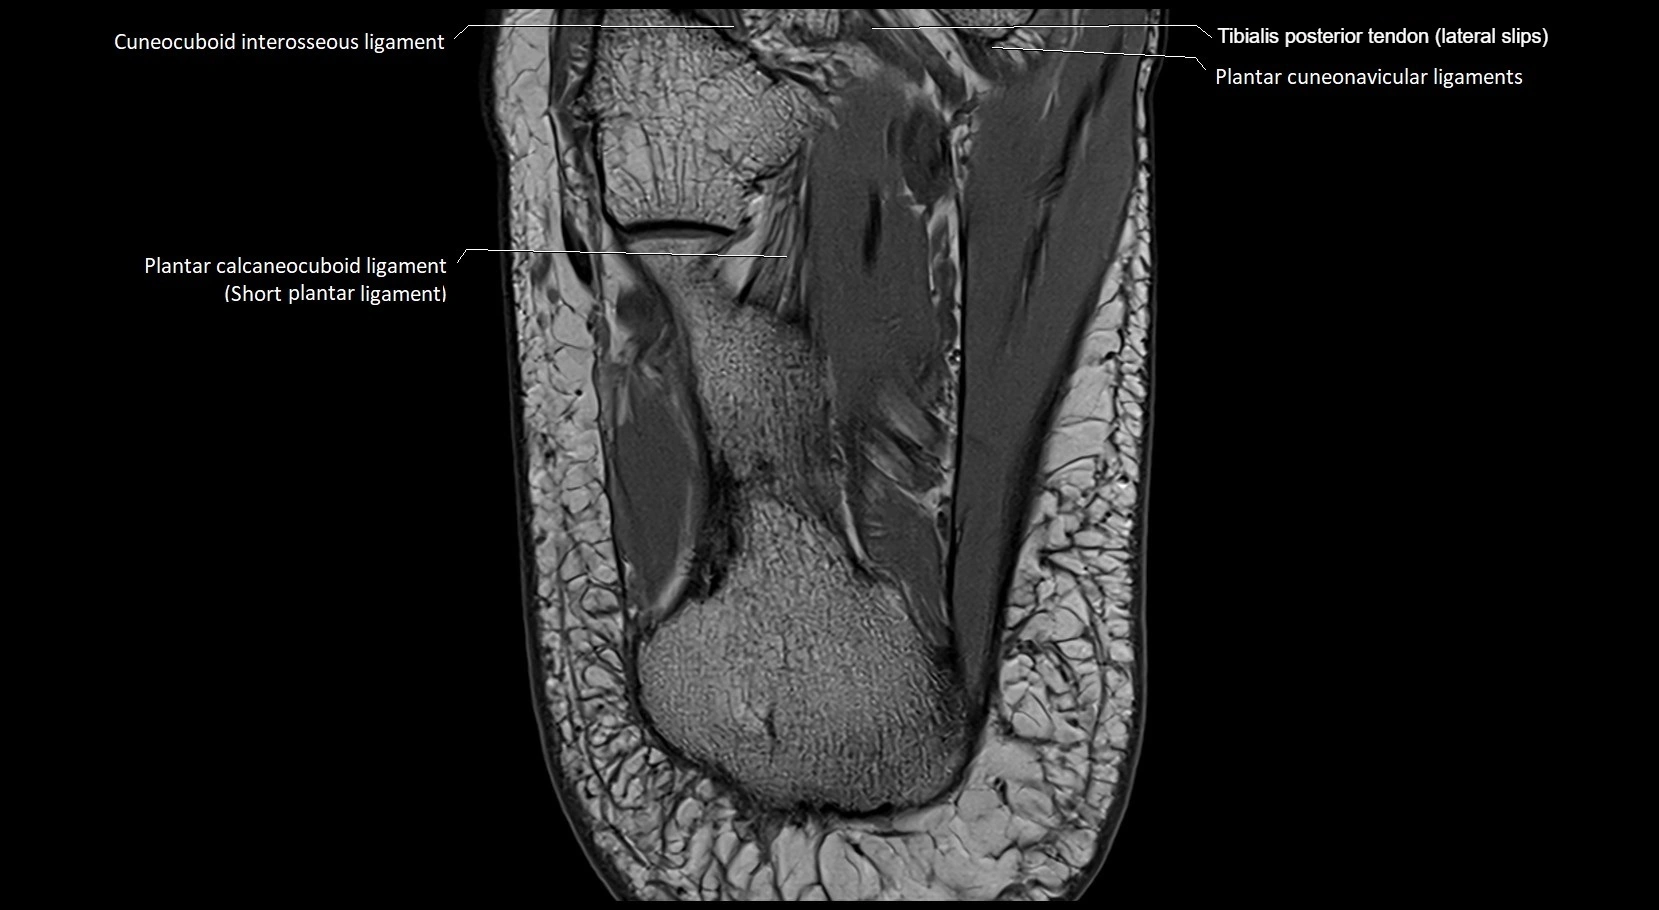

MRI image

image